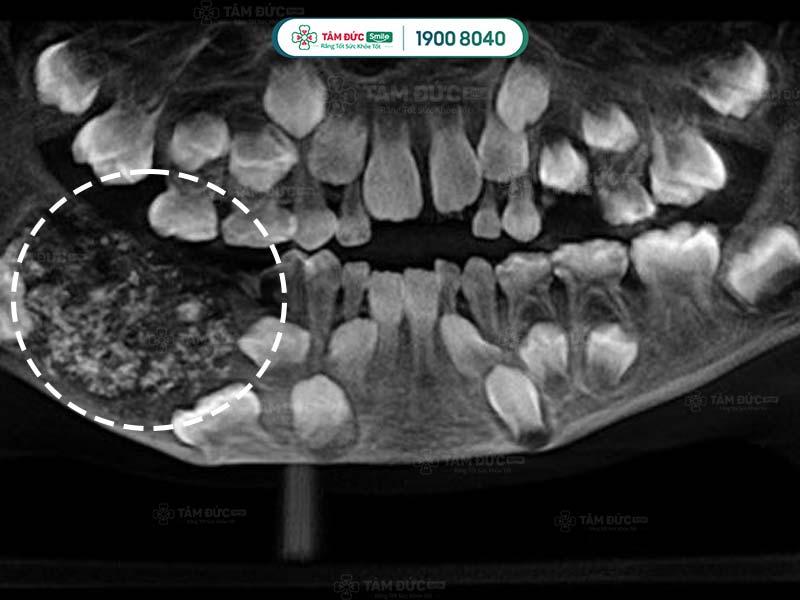

5.2. Chụp CT scan cho u răng

Sử dụng phương pháp chụp CT Scan để nhìn thấy rõ được cấu trúc bên trong khối u răng đó như thế nào.

Trong một số trường hợp cần thiết như u răng phức hợp phát triển vào khoang mũi. Cần thực hiện thêm 1 số xét nghiệm khác như chụp cộng hưởng từ MRI… Để có thể đưa ra được phương pháp điều trị phù hợp.